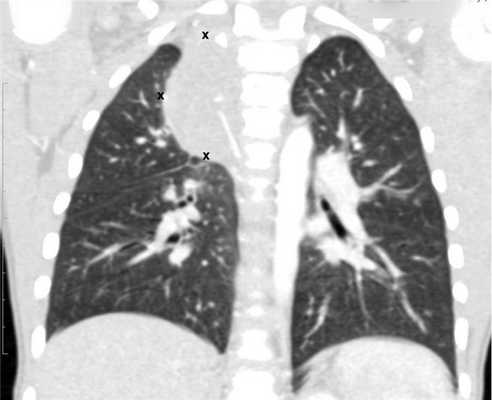

Рисунок 6. — КТ органов грудной клетки - семинома средостения.

- Рентгенография органов грудной клетки (данное обследование обязательно, потому что оно дает возможность подтвердить диагноз при первичных новообразованиях средостения и наличии метастазов в легких).

- КТ (расшифровка: компьютерная томография), МРТ (расшифровка: магнитно-резонансная томография), ПЭТ-КТ (расшифровка: позитронно-эмиссионная томография, совмещенная с КТ). Эти обследования необходимы, чтобы рассмотреть структуры организма послойно и визуализировать опухоль. Они показывают, как сильно распространен патологический опухолевый процесс на находящиеся рядом ткани и органы, есть ли поражение костей. КТ - это самый чувствительный метод для обнаружения метастазов в легких. Проведение МРТ и КТ головного мозга необходимо, чтобы обнаружить и визуализировать герминогенные новообразования эпифиза.